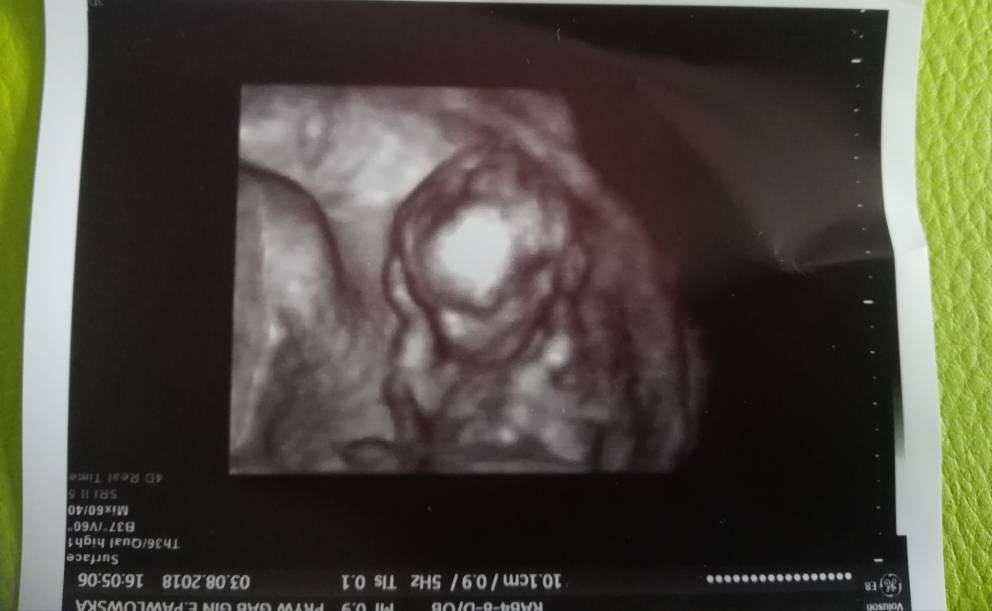

Przepraszam że tak długo się nie odzywałam ale po wizycie poszłam do siostry zagadaliśmy się i dopiero niedawno wróciłam, dziękuję za wszystkie kciuki [emoji8][emoji8][emoji8]

Wszystko jest dobrze i na 100% będzie syn! Jestem w siódmym niebie [emoji7][emoji7][emoji7]Lekarz musiał zrobić USG dopochwowe żeby sprawdzić czy nie skraca mi się szyjka i wtedy na pierwszym miejscu ukazał się siusiak ,więc tu nie ma wątpliwości [emoji846]Dzisiaj miałam robione USG na takim lepszym sprzęcie więc wszystko było widać perfekcyjnie,badał go bardzo dokładnie ale nie mówił jakie wymiary a ja się nie pytałam bo byłam wpatrzona w mojego małego mężczyznę [emoji1]Pierwszy raz był zemną mąż i jestem wzruszona, nigdy nie widziałam u niego takiego stresu i jakby dumy ,niewiem jak to opisać ale to był najpiękniejszy dzień w moim życiu [emoji7]

Jeżeli o mnie chodzi z szyjką wszystko wporzadku ,powiedział że jest trochę skrzywiona ale to nic groźnego, kazał brać mi magnez [emoji6]Na plusie tylko 1.3kg więc spoko a no i ze względu na kołatania serca mam się udać w połowie ciąży do kardiologa sprawdzić czy to nie jest nic groźnego [emoji846]

Jeżeli o mnie chodzi z szyjką wszystko wporzadku ,powiedział że jest trochę skrzywiona ale to nic groźnego, kazał brać mi magnez [emoji6]Na plusie tylko 1.3kg więc spoko a no i ze względu na kołatania serca mam się udać w połowie ciąży do kardiologa sprawdzić czy to nie jest nic groźnego [emoji846] Zobacz załącznik 884701Zobacz załącznik 884702